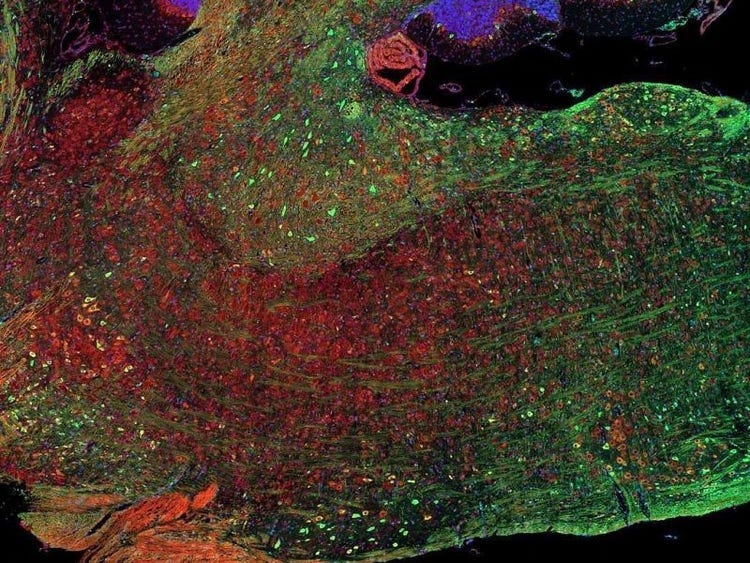

Fluorescence imaging of a mouse brain

Cette vue d’un cerveau de souris est en réalité constituée par l’assemblage d’une multitude d’images prises par imagerie de fluorescence.

Le scientifique britannique Sir George G. Stokes a d’abord constaté que la fluorine minérale devenait fluorescente lorsqu’elle était éclairée par une lumière ultraviolette, et il a inventé le mot « fluorescence ». Stokes a remarqué que la lumière fluorescente présentait des longueurs d’onde supérieures à celles de la lumière d’excitation, un phénomène aujourd’hui connu sous le nom de « déplacement de Stokes ». La microscopie de fluorescence est une excellente méthode pour étudier une matière qui peut devenir fluorescente soit sous sa forme naturelle (appelée fluorescence primaire ou autofluorescence), soit lorsqu’elle est traitée avec des produits chimiques qui peuvent devenir fluorescents (appelée fluorescence secondaire).